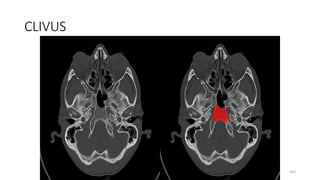

CLIVUS

163